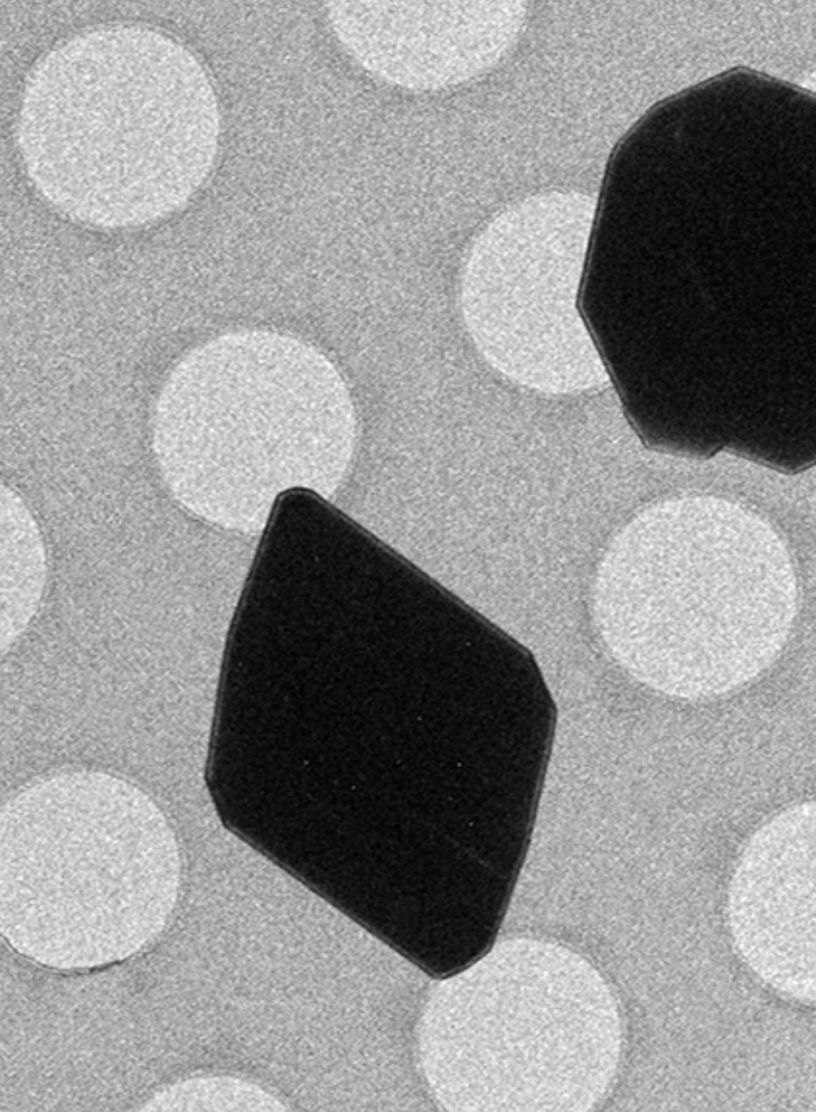

用电镜获取微米级颗粒的分子结构

8. 新技术数分钟内可确定分子结构

2018年10月,两个研究小组同时发表论文,揭示了在几分钟内确定小有机化合物分子结构的新方法。研究人员通过用电子束替换 X 射线来改进衍射技术,电子束瞄准目标生物大分子的片状2D晶体堆叠而成的微小3D晶体。他们向旋转台上的微小3D晶体发射电子束,并跟踪每次轻微旋转时衍射图案的变化情况。该技术可在几分钟内产生来自微观晶体的分子结构。新技术非常适合用于绘制激素和潜在药物等小分子结构,将对新药的合成和发现、分子探针设计,以及研究和追踪疾病等领域产生深远的影响。